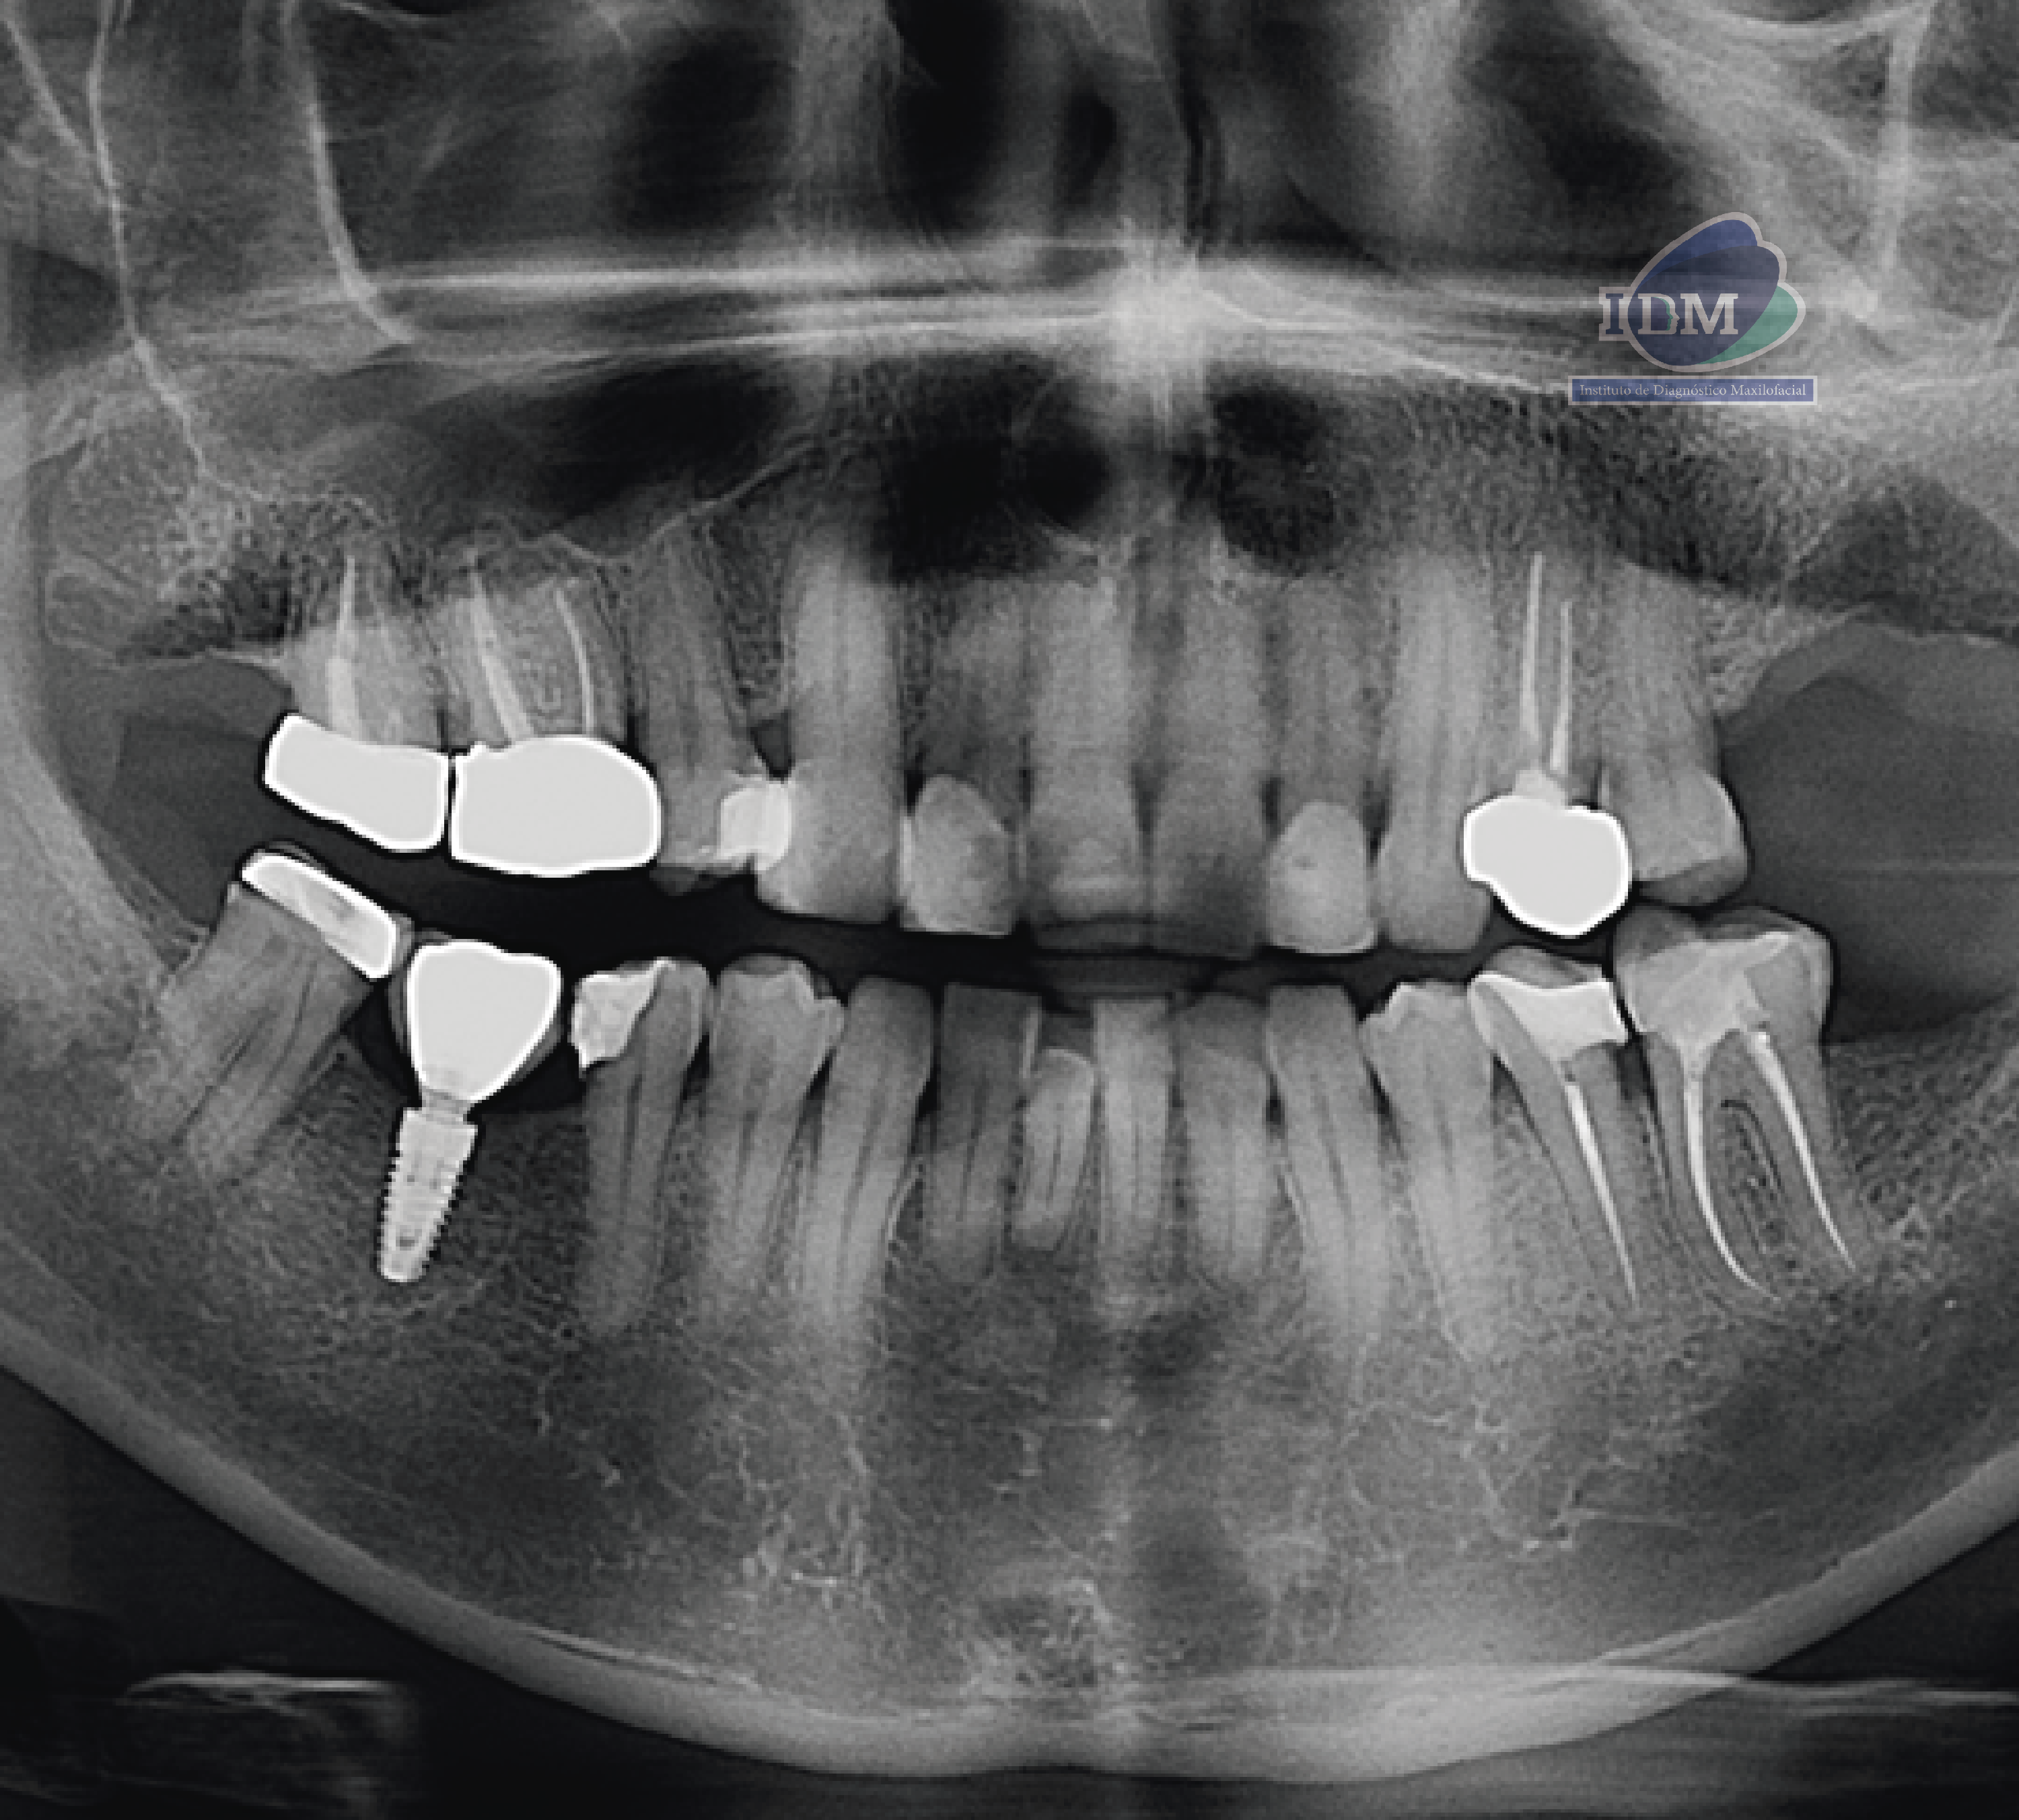

Paciente masculino de 55 años, es referido al Instituto de Diagnóstico Maxilofacial – IDM (Sede Surco) para planificación de implantes dentales. Radiografia Panorámica En la